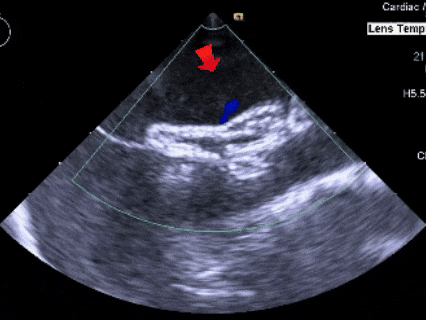

测量膨出瘤基底宽19.61mm,深7.00mm

房间隔总长44.22mm,缺损大小14.80mm

超声可见房间隔连续中断,彩色多普勒可见过隔血流

三维下可见房间隔缺损